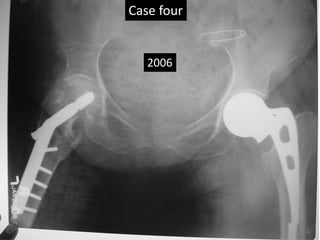

Case Four

1992

2000

2006

Case Three • Thisold man had AMP left hip before 1992 (X- rays) • He had fracture trochanter on right side – 2000. • DHS was done in 2000. • Last follow up 2006. • Rigid fixation by bone in fenestrations. • Medial migration of distal loose piece.